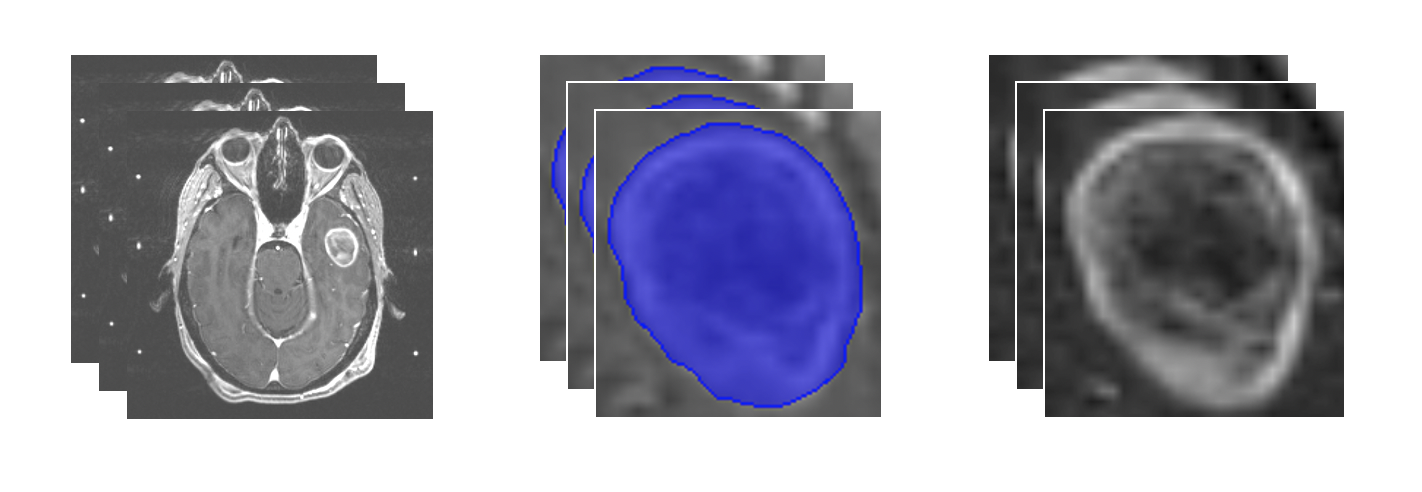

- Input: Slices of brain MRI scans loaded from DICOM files

- Identification of region of interest: Tumor segmentation

- Output: Extracted tumor of interest